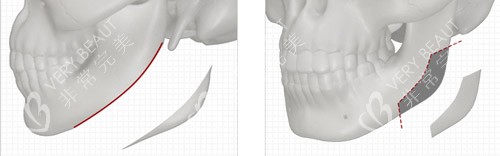

什么是智能化更准截骨

李运峰较早引入3D技术辅助手术。术前用CT数据重建三维骨骼模型。可在术前模拟术后结果并进行方案设计。术中采用导航系统实时追踪截骨位置。将截骨误差控制在极低范围内。

针对不同脸型的方案设计

圆脸侧重颧骨适度调整并保留饱满度。长脸注意控制比例避免进一步拉长。菱形脸重点内推颧弓塑造流畅线条。所有方案都遵循面部美学比例。